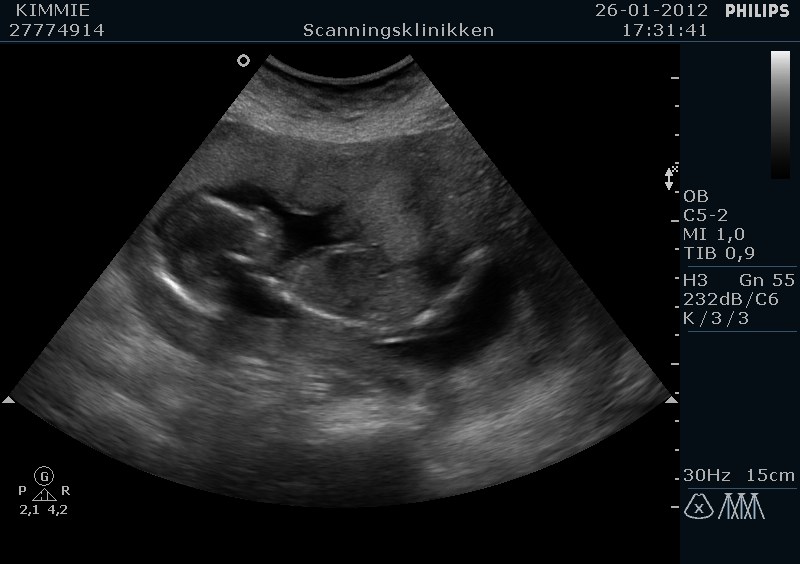

Jeg havde en tyk moderkage som lå ud mod maven og derfor var babs godt gemt, så det tog lidt ekstra tid for at 100 % at kunne identificere kønnet.

Men den er god nok, vi venter en lille....... PIGE mere...

Til sidst lige et par billeder

Vedhæftede fotos (klik for at se i fuld størrelse)